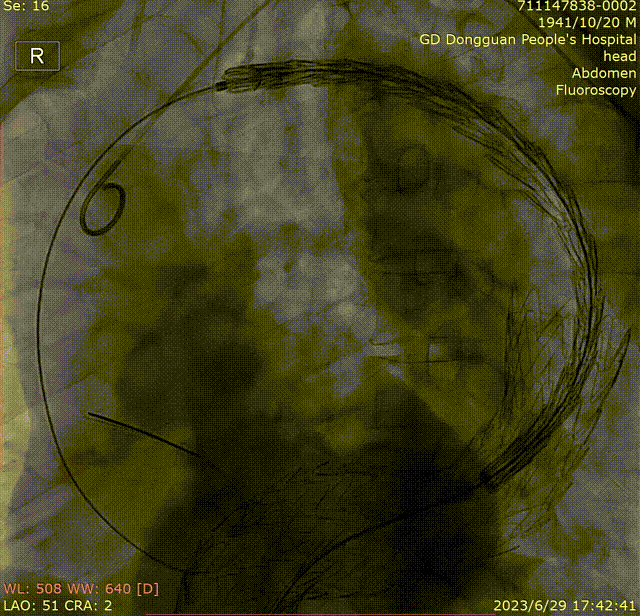

手术过程

1.经左侧股动脉切开直视下穿刺入路,股动脉真腔狭小,近端完全闭塞,开通困难,小剂量多次造影确认真腔,建立真腔通路。

gore医疗怎么样「胸有乾坤」危如累卵 妙手回春——Conformable GORE®TAG®胸主动脉覆膜支架应用于高龄急性主动脉夹层治疗_https://www.jmylbn.com_新闻资讯_第21张

gore医疗怎么样「胸有乾坤」危如累卵 妙手回春——Conformable GORE®TAG®胸主动脉覆膜支架应用于高龄急性主动脉夹层治疗_https://www.jmylbn.com_新闻资讯_第22张

2.交换猪尾导管,行整体造影,如图所示。